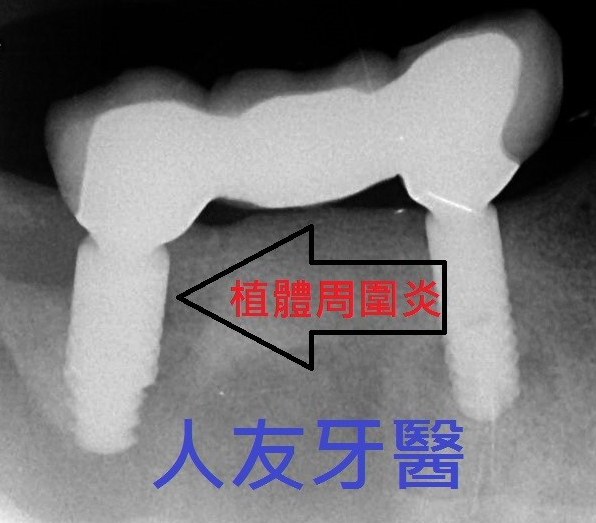

植牙後怎麼保養 ?